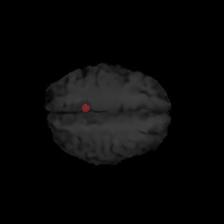

Brain tumor segmentation. Segmenting tumors in brain is challenging due to the high variance in appearance and shape of the tumors [28]. We use a subset of the 2017 Brain Tumour Image Segmentation (BraTS) dataset [29, 26]. It contains multi-parametric 3D MRI scans. The segmentation masks include (possibly overlapping) three classes of tumor. The 3D scans are split into 2D image slices, and only images that contain at least one tumor class are retained. Figure 7 shows three MSGNet generated samples as well as the corresponding masks. Since MSGNet adheres to the underlying relationships between various classes, we see that the generated images and the masks for different tumor classes are in line with the images and masks from the training set. In general, MSGNet rarely generated erroneous samples; we found roughly one sample per 3000 generations that could be rejected. Similar to the malaria experiment, we observed an improvement of 3.1% () in -score on the validation set.

A subset of the BrATS dataset was used. We used the images accompanied by segmentation layouts from the FLAIR and T1Gd modes. The segmentation layouts showed the sub-regions for three different classes: GD-enhancing tumor, the peritumoral edema, and the necrotic and non-enhancing tumor core. The brain and the background were treated as an additional class. We refer to [32] for further details. For the two modes, the background has been modelled using two different classes. We only considered half of the 155 slices, i.e., we took only the even-numbered slices and out of those we discarded the slices that did not include one of the previously mentioned tumor-classes in order to create a more balanced dataset. This resulted in 20,000 images that were further augmented with 6,000 MSGNet generated images. Example generations of the masks as well as the images are shown in Figure 12.